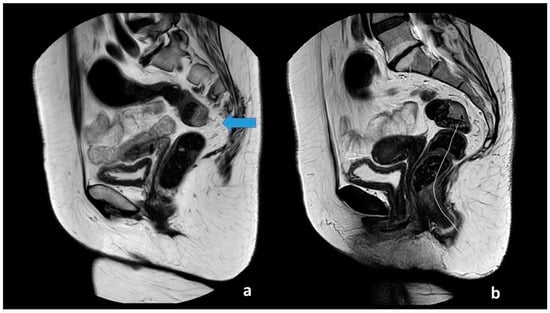

All images had a quality check by one of two authors (M.R.V.P and S.R.R). The two observers received a basic instruction on how to perform the assessment of the anal verge and takeoff, defined as the point from which the sigmoid sweeps horizontally away from the sacrum. The observers used the sigmoid blood vessels insertion as an adjunct in the determination of the location. The two observes measured the distance from the anal verge to the sigmoid takeoff using a curved digital ruler. The measurement of the anal verge and takeoff is visualized in Figure 1. The observers were blinded to the patient history, diagnosis, and prior image investigations. T2W-weighted MRI images with 3 mm slice thickness were used to perform the measurements.

Figure 1. Sagittal T2-weighted images from a 65-year-old female patient with a T1 tumor located at the posterior wall just above the sigmoid takeoff. The arrow indicates the sigmoid take-off from which the sigmoid sweeps horizontally away from the sacrum and with the sigmoid blood vessels insertion (a). The takeoff and the lower border of the tumor is located 11 cm above the anal verge (b).